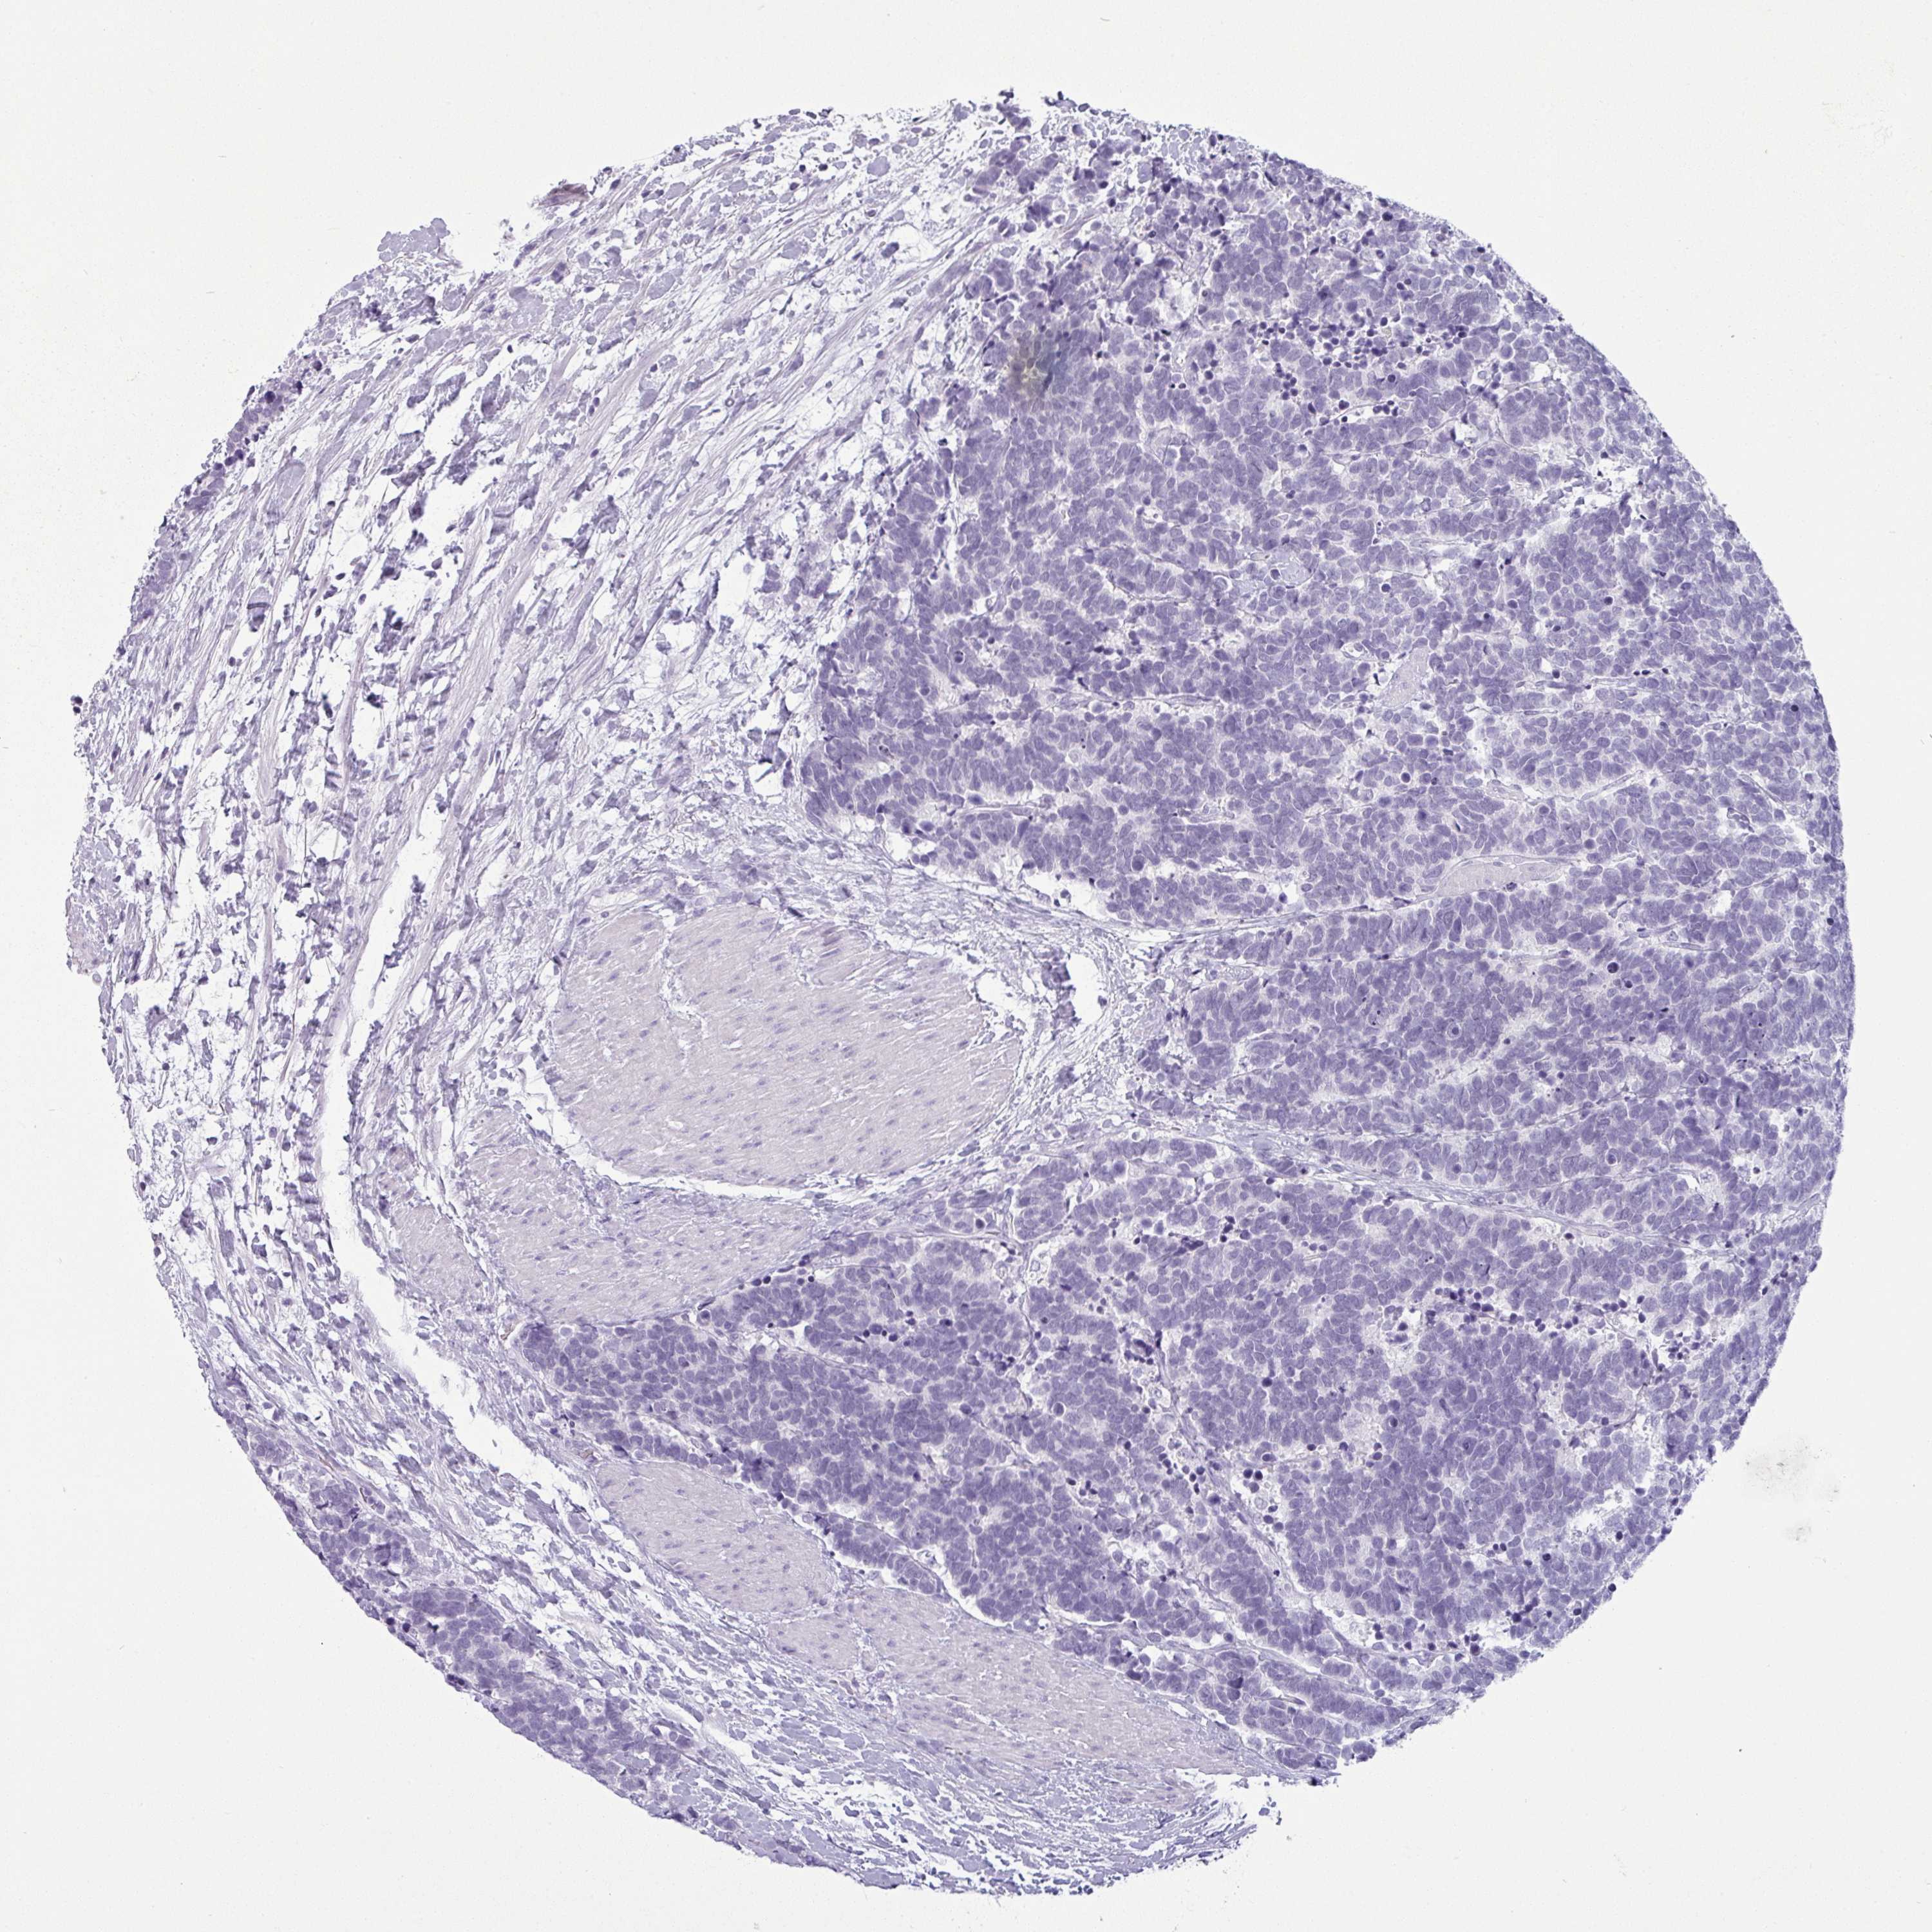

CARCINOID - Protein expressioni

A mouse-over function shows sample information and annotation data. Click on an image to view it in a full screen mode. Samples can be filtered based on level of antibody staining by selecting one or several of the following categories: high, medium, low and not detected. The assay and annotation is described here.

Each image is clickable and will lead to virtual microscopy that enables deeper exploration of all samples and also displays staining intensity scores, fraction scores and subcellular localization as well as patient and tissue information for each sample.

Antibody HPA036260

Staining

High

Medium

Low

Not detected

Intensity

Strong

Moderate

Weak

Negative

Quantity

>75%

75%-25%

<25%

None

Location

Nuclear

Cytoplasmic/membranous

Cytoplasmic/membranous,nuclear

Carcinoid, malignant, NOS

Carcinoma, NOS